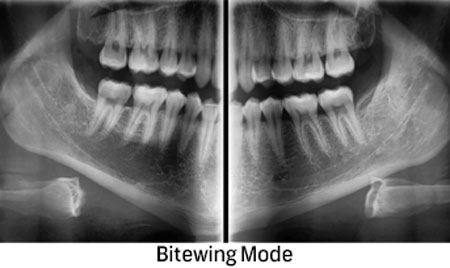

2D и 3D CBCT РТГ ДИГИТАЛНА ДИЈАГНОСТИКА

Преку нашите истражувачки активности, нашиот тим е запознаен со најновите научни наоди и може да ги исполни највисоките технолошки и професионални очекувања. За прегледи и проценки, имаме широк спектар на опции. Користиме различни методи за сликање, како што се проекциона радиографија, томографија и компјутерска томографија.

Kористиме најнова технологија за да овозможиме прецизен третман за нашите пациенти преку методи на снимање.